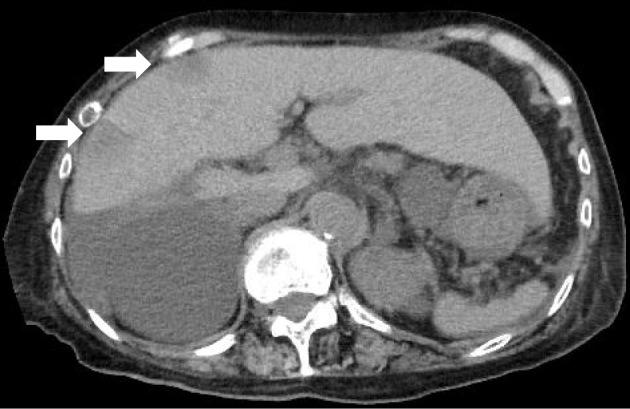

Sister Mary Joseph's Nodule from Pancreatic Cancer.

Sister Mary Joseph's Nodule from Pancreatic Cancer.源自胰腺癌的玛丽·约瑟夫修女结节